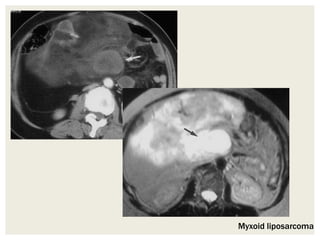

• Myxoid liposarcomas are of intermediate-grade malignancy

and have a CT attenuation lower than that of muscle but

greater than fat.

• They are homogeneously hypointense on T1-weighted MR

images and markedly hyperintense on T2-weighted images.

• In addition, they may appear cystic before contrast

enhancement but show gradual reticular post contrast

enhancement

• Myxoid liposarcomas may coexist with other subtypes of

liposarcomas.

Myxoid liposarcoma